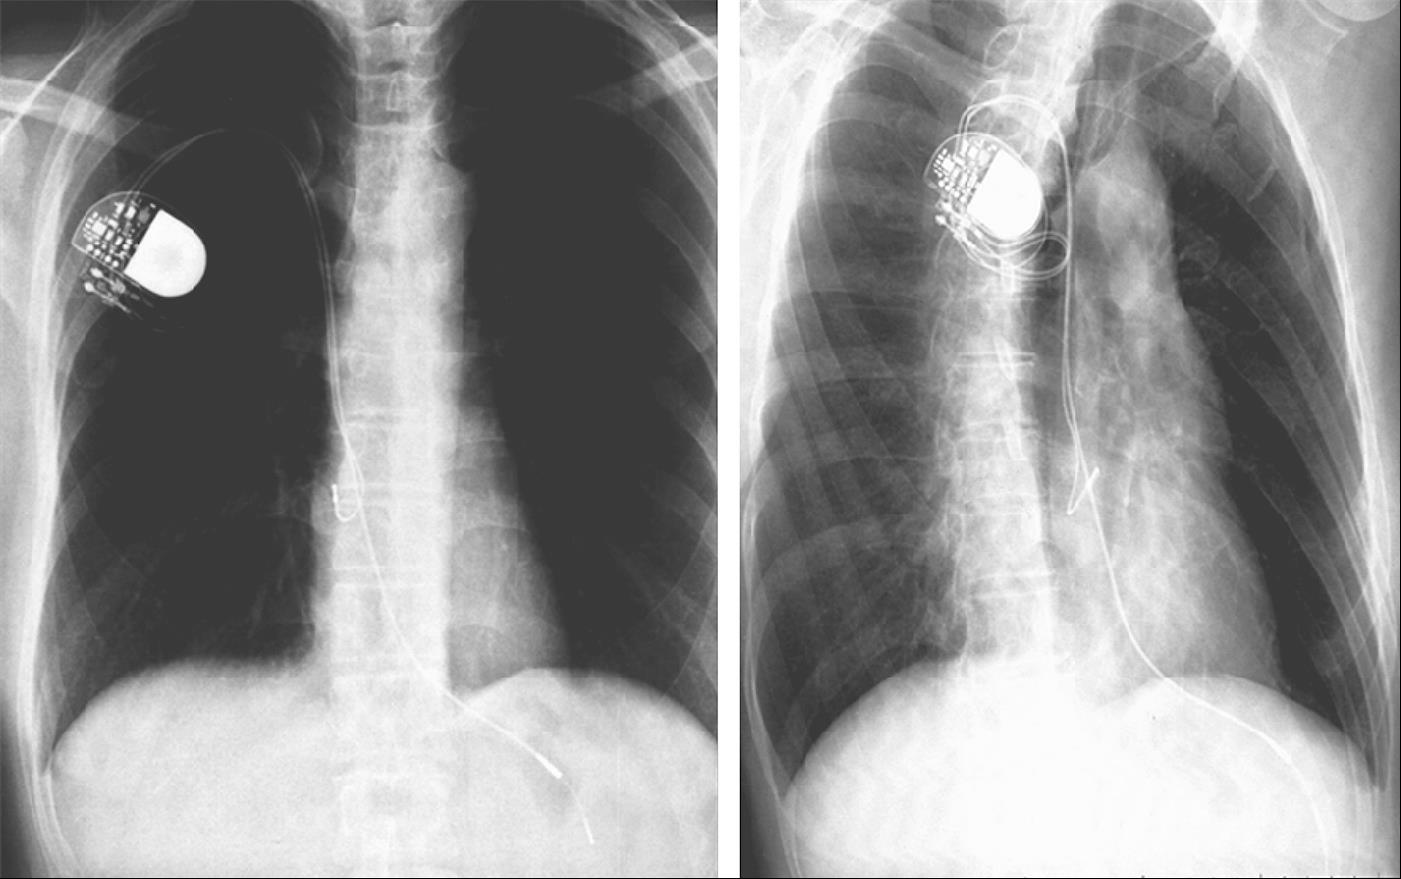

图1-16 导线脱位

心房导线脱位至上腔静脉。